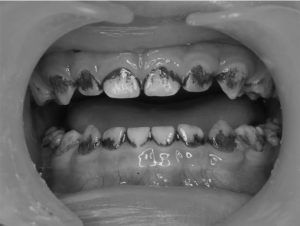

Với khẩu hiệu “Nụ cười hạnh phúc, tương lai rạng ngời” (Happy smiles, bright futures), chúng tôi mong muốn rằng Chi hội Nha Khoa Trẻ Em Việt Nam sẽ không chỉ là nơi để các nhà chuyên môn giao lưu, học hỏi mà còn là nơi chúng ta cùng nhau xây dựng những giá trị tốt đẹp cho thế hệ tương lai. Sự phát triển toàn diện của trẻ em không thể thiếu một sức khỏe răng miệng tốt, và chúng tôi cam kết sẽ đồng hành cùng các em trên hành trình chăm sóc sức khỏe này.